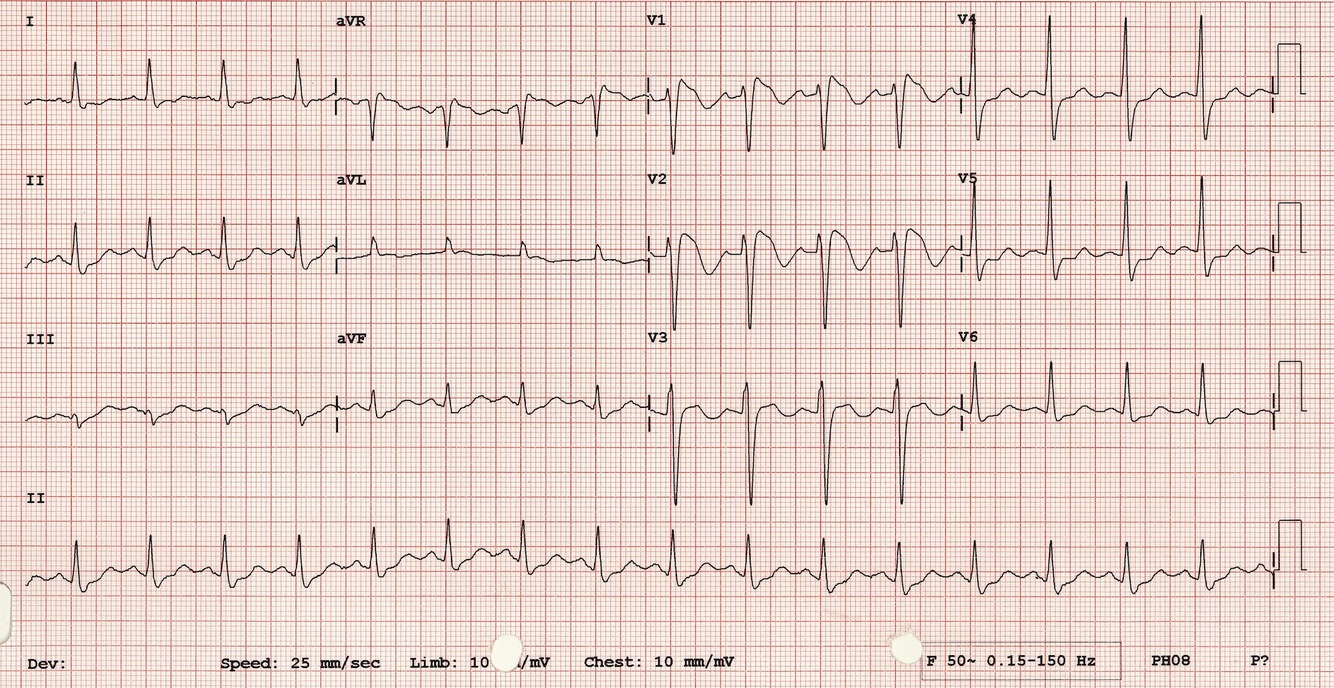

What disease is shown on this ECG?

Wolff-Parkinson-White syndrome - short PR interval with a delta wave before the Q wave